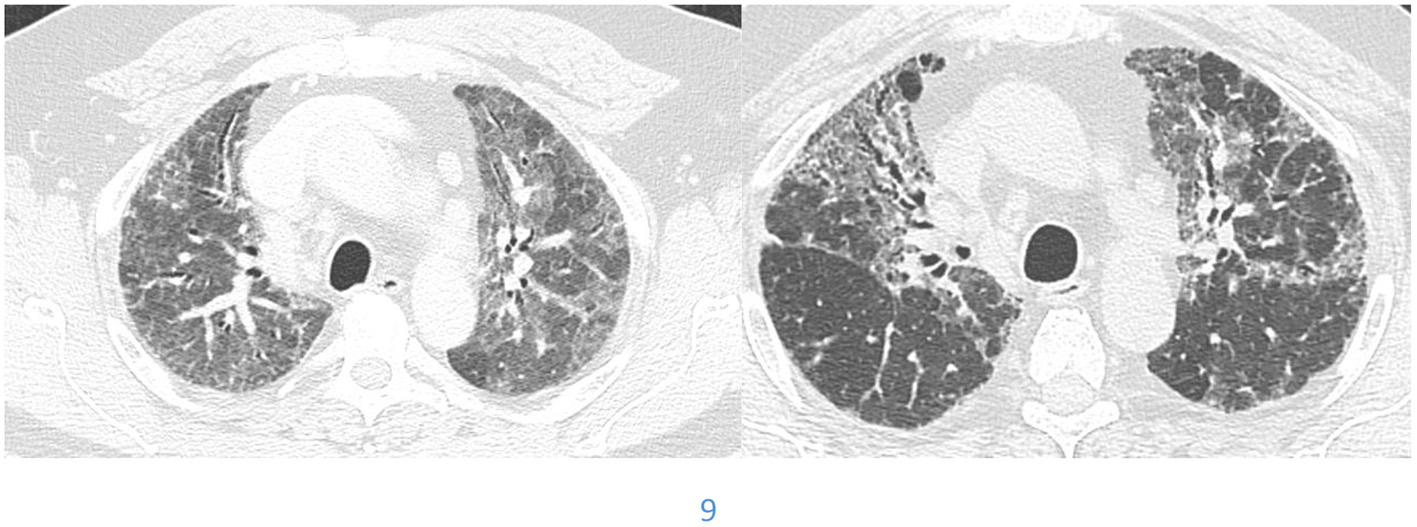

Sarcoidosis

There are basically two main types of sarcoidosis, fibrotic and non-fibrotic (32). The non-fibrotic type of sarcoid has pulmonary nodules and lymphadenopathy (Figure 6). The major feature of the progression of the fibrotic type of disease is volume loss with tenting of the hemi-diaphragms. Fibrotic sarcoid primarily affects the posterior aspect of the upper lobes and as such displaces the right upper lobe bronchus (32). In particular, the radiologist can measure the angle between a line traversing the right upper lobe bronchus and a sagittal line connecting the sternum to the vertebral body. The angle is called the Right Upper Lobe Bronchus Angle (RUL-BA) (Figure 7). The angle increases with the fibrotic phase of the disease and can be used as a biomarker for disease progression (32).

Figure 6

Non-fibrotic sarcoidosis with pulmonary nodules in a peri-lymphatic distribution.

Figure 7

Stage 4 sarcoidosis is associated with progressive loss of volume of the upper lobes with displacement of the right upper lobe bronchus posteriorly as seen in this image.